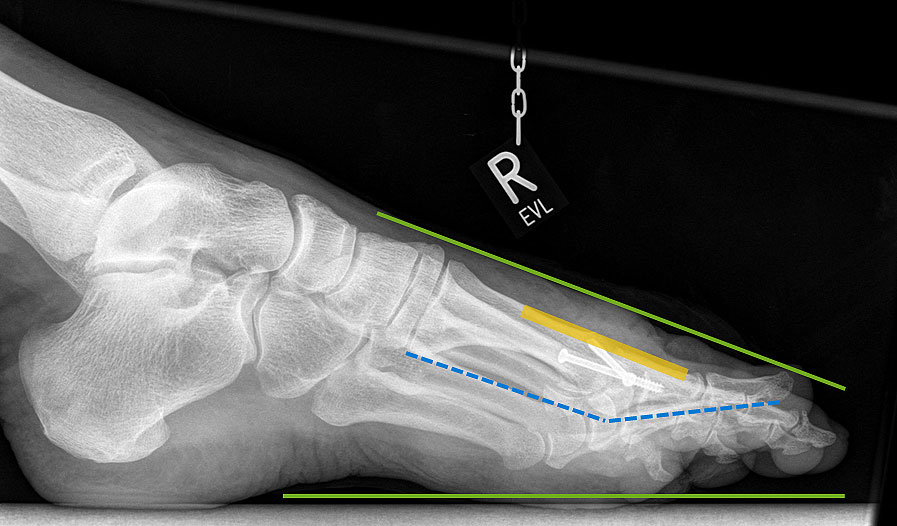

Die Röntgenaufnahmen (Abbildung 1) zeigen den Fuß einer 34 jährigen Patientin nach Exostosenabtragung. Der erhöhte intermetatarsale Winkel wurde durch eine alleinige Abtragung der Exostose nicht reduziert. Als weiterer Risikofaktor für ein Rezidiv liegt ein pathologischer Gelenkwinkel vor. Der intermetatarsale Winkel von 18 Grad kann durch eine basisnahe Osteotomie gut korrigiert werden. Da durch die gleichzeitige distale Korrektur des Gelenkflächenwinkels mithilfe einer Reverden-Green Osteotomie ein Längenverlust von ca. 2-4 mm einhergeht, bot sich als proximales Korrekturverfahren die basisnahe Open-wedge Osteotomie an, um bezüglich der Länge des Metatarsale I neutral zu bleiben (Abbildung 2). Die Kombination zweier verkürzender Verfahren (z.B. Lapidus und Reverden-Green) würden zu einem sehr kurzen ersten Strahl führen, mit dem Risiko einer Transfermetatarsalgie. Übersteigt die Verkürzung des Metatarsale I 2 mm, steigt das Risiko für die Entwicklung einer Transfermetatarsalgie deutlich an 8. Die durchgeführte Revision zeigt eine gute Stellung des 1. Strahls bei zentriert stehendem Gelenk.